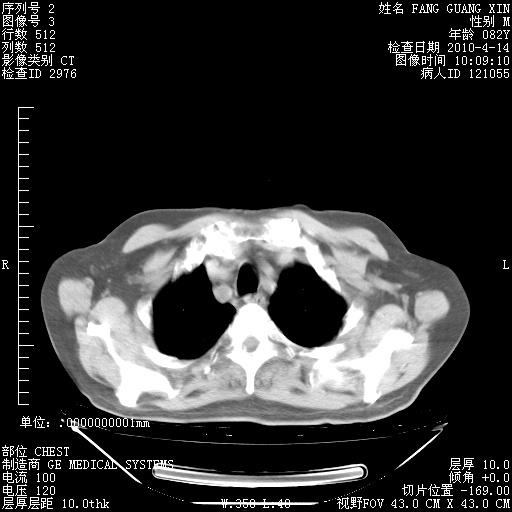

肺部CT平扫未见异常。